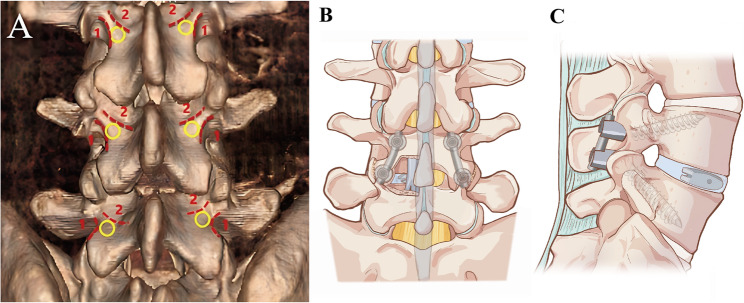

Results: Basic demographic data, fusion rates, postoperative hospital stays, and follow-up times did not significantly differ between the two groups. Compared with those in the M-TLIF group, the intraoperative blood loss (68.57 ± 14.84 mL) and postoperative drainage volume (33.93 ± 9.17 mL) in the M-MIDLIF group were lower (intraoperative blood loss: 171.79 ± 12.78 mL, p < 0.05; postoperative drainage volume: 65.36 ± 10.36, p < 0.05). In the M-MIDLIF group, there was no significant difference in the radiographic recognizable rate (91.07%) or intraoperative visual recognizable rate (87.50%) of internal inverted chevron-shaped (V-shaped) crests. The optimal position screw rates for the MCBT, TASS, and traditional pedicle screw (TPS) methods were 94.64%, 94.64%, and 87.5%, respectively, and the differences were not significant. MCBT technology preserved the integrity of the posterior ligamentous complex (PLC) in 92.85% of patients in the M-MIDLIF group. The facet joint violation (FJV) rate of MCBT screws (3.57%) was lower than that of TPS screws (14.29%). Compared with the M-TLIF group, the M-MIDLIF group presented greater reductions in the ODI and VAS scores for both low back and leg pain at 1 week postoperatively (P < 0.05). However, no statistically significant differences in these scores were observed between the two groups at later time points (p > 0.05).